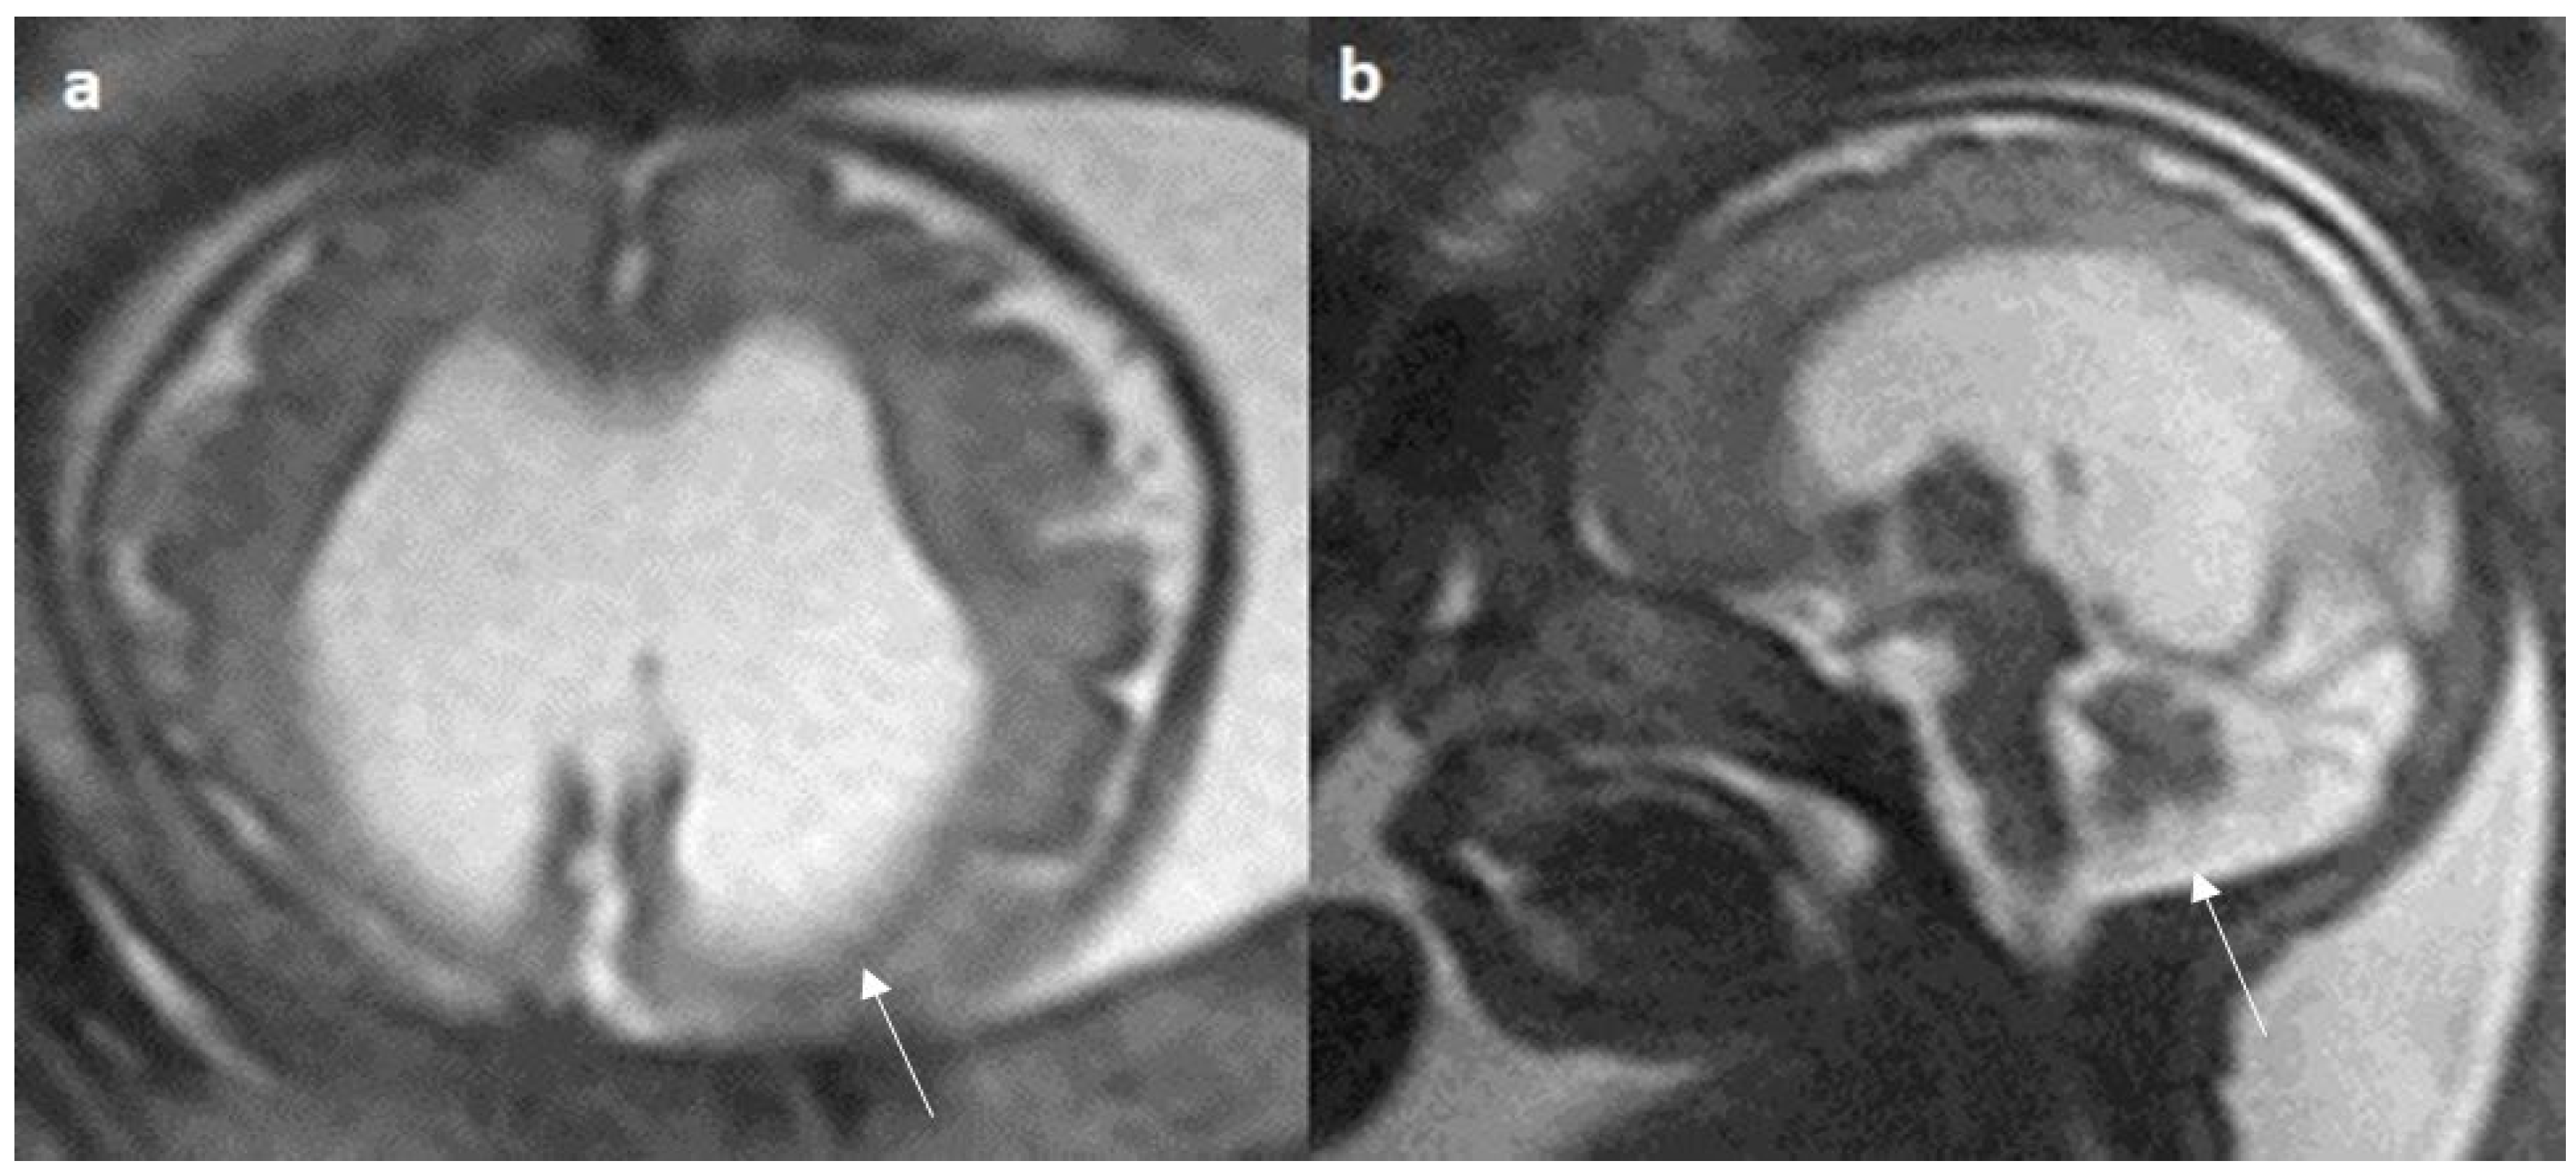

Figure 6.

Fetal MRI images of a 29 gestational weeks aged fetus in a case of hypoplasia with dysplasia of the corpus callosum. (a) A T2-weighted sequence in axial plane showing severe dilatation of the lateral ventricles, particularly at the body and atria, with thinning of the brain parenchyma in the posterior parieto-occipital region, and an associated absent cavum septum pellucidum was noted (white arrow). (b) A T2-weighted sequence in midsagittal plane shows thin anterior corpus callosum with dysplasia. Additionally, hypoplasia of the inferior vermis is noted (white arrow).

Figure 7.

Fetal MRI images of a 20 gestational weeks aged fetus with complete agenesis of the corpus callosum. (a) A T2-weighted sequence image in axial plane showing non-decussating anterior-posterior white matter tracts known as Probst bundles medial to the lateral ventricles (arrow). (b) A T2- weighted sequence coronal image showing Probst bundles indenting superomedial margins of lateral ventricles. Probst bundles are seen with complete agenesis of the corpus callosum.